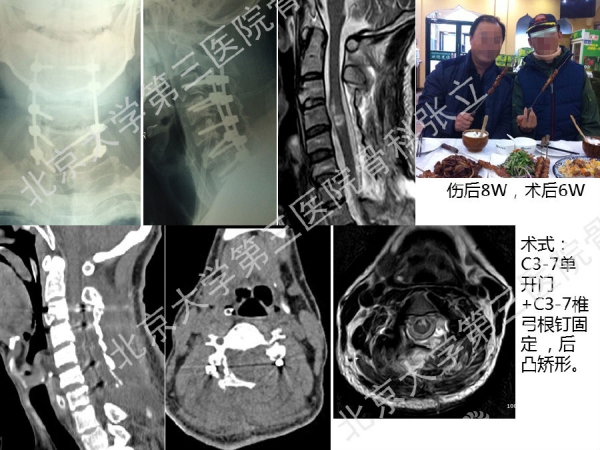

徒手置钉的下颈椎椎弓根钉技术对于很多骨科同道来说,无疑是难度超高、不敢触及的一项技术。已熟练掌握这一技术的北京大学第三医院骨科张立主任医师认为,下颈椎椎弓根钉徒手置钉技术固定可靠,能满足绝大多数后路固定所需,可应用于脊柱外伤、脊柱畸形、脊柱肿瘤,以及CSM伴退变性颈椎后凸畸形。它的优势是:螺钉尾部靠外,不影响椎板成形术;先置钉固定,后开门,更安全;和椎板成形术完美结合,减压、复位、固定一次完成;极少出现脊髓、神经根及椎动脉损伤。